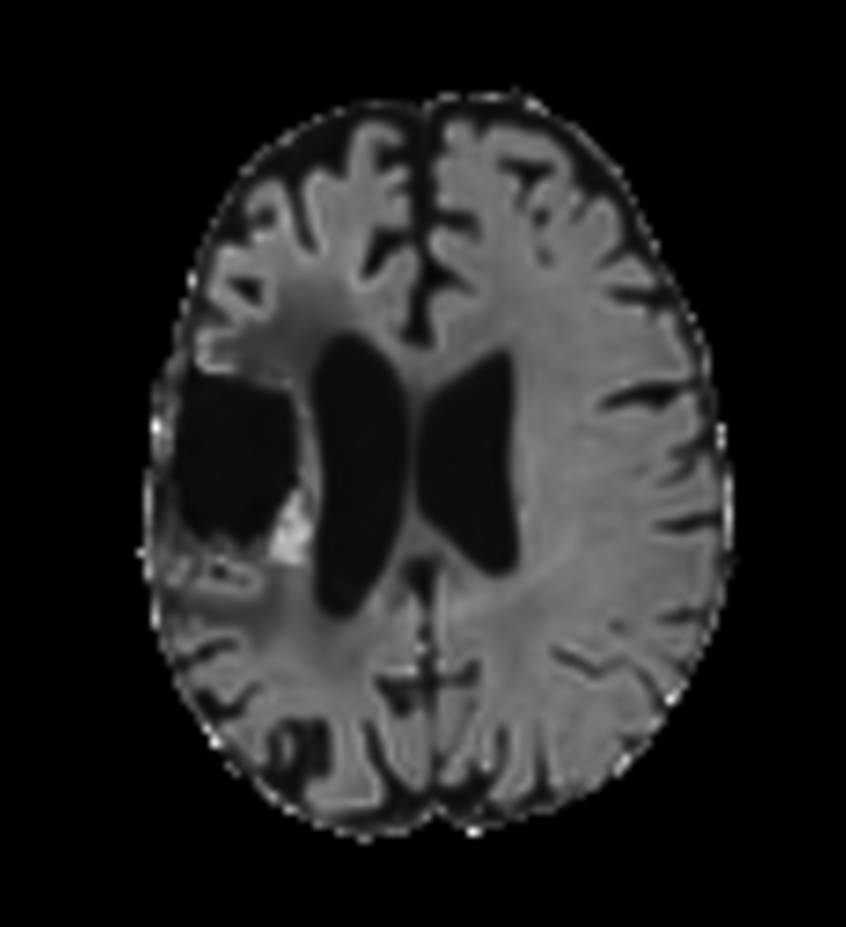

Brain glioblastoma, post-operative

Patient who was operated on glioblastoma

Axial DTI (ADC)

-

Axial DTI (eADC)